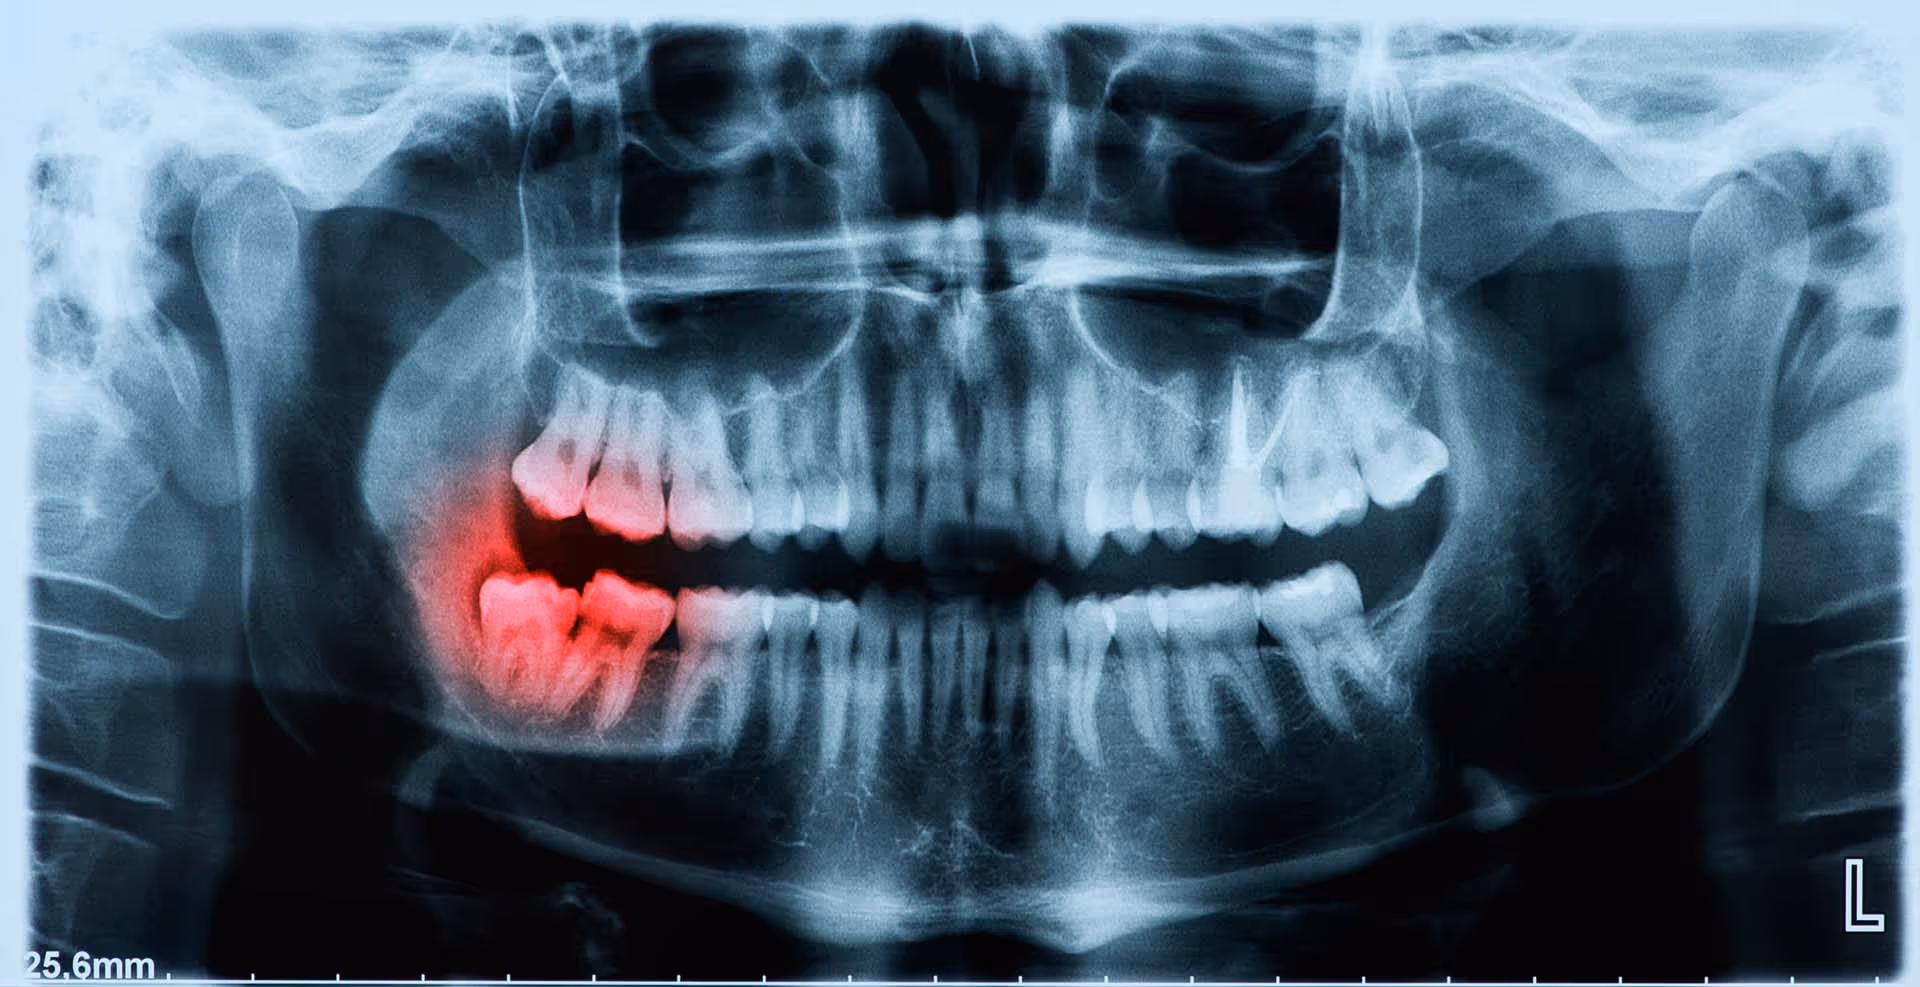

Wisdom teeth, also known as third molars, typically emerge between the ages of 17 and 25. However, due to lack of space in the jaw, these teeth often fail to erupt properly, becoming impacted. Impacted wisdom teeth can cause pain, swelling, infections, and misalignment of surrounding teeth, making removal necessary to prevent complications.

Impacted wisdom teeth occur when there is not enough space in the mouth for proper eruption. Instead of growing in straight, they may:

- Remain trapped under the gums

- Grow sideways, pressing against other teeth

- Erupt partially, leading to infections

- Cause cysts or damage surrounding bone

Types of Impacted Wisdom Teeth

1. Soft Tissue Impaction

The wisdom tooth is partially covered by gum tissue, making it difficult to clean and prone to infection.

2. Partial Bony Impaction

The tooth is partially covered by both gum tissue and jawbone, making eruption painful and problematic.

3. Complete Bony Impaction

The wisdom tooth is fully trapped within the jawbone, requiring surgical extraction to prevent damage to surrounding teeth and bone.